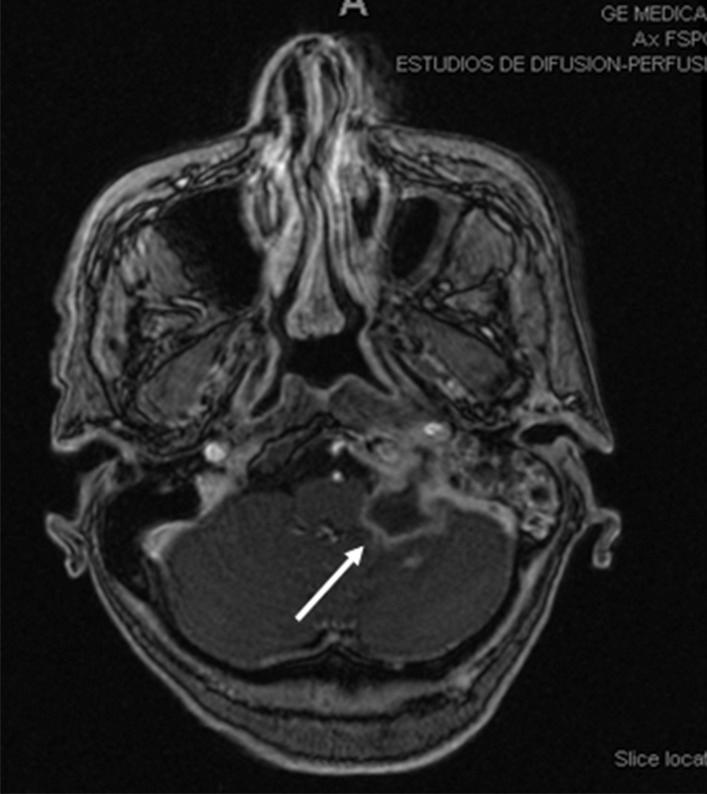

A 59-year-old caucasian female with radioactive iodine-refractory metastatic thyroid papillary carcinoma with BRAF mutation was treated with dabrafenib and trametinib as a compassionate use. After 4 months treatment, positron emission tomography-computed tomography (PET-CT) showed PI. At the time of diagnosis, the patient was asymptomatic without signs of peritonitis. The initial treatment was conservative and no specific treatment for PI was needed. Unfortunately, after dabrafenib-trametinib withdrawal, the patient developed tumor progression with significant clinical worsening.

一位 59 岁的白人女性,患有放射性碘难治性转移性甲状腺乳头状癌,BRAF 突变,接受了达布拉非尼和曲美替尼的同情治疗。治疗 4 个月后,正电子发射断层扫描-计算机断层扫描(PET-CT)显示有 PI。在诊断时,患者无症状,无腹膜炎迹象。初始治疗为保守治疗,无需针对 PI 的特殊治疗。不幸的是,在停用达布拉非尼-曲美替尼后,患者出现肿瘤进展,临床状况显著恶化。